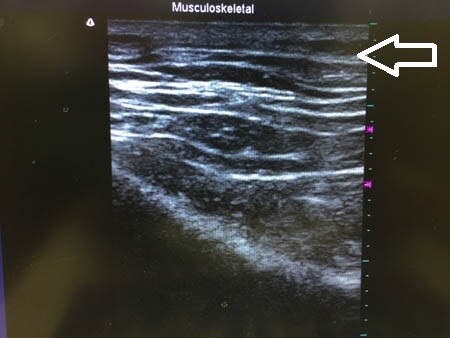

下腹部も同様に見てみましょう。

↓ ↓ ↓